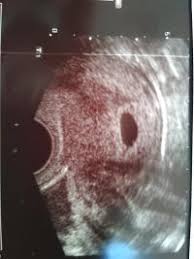

War das erste mal letzten do beim gyn aufgrund eines positiven sst im ultraschall konnte man fruchthöhle und dottersack sehenalles gut sagte sieheute war ich nochmal da also eine woche später56 und man hat im ultraschall nur gesehen das die früchthöhle ne ganze ecke gewachsen ist und das der dottersack zu sehen istsie vermutet am dottersag minimale embryonale anlagen aber ist. SSW 55 Ultraschall keine Fruchthöhle. War am 247.

Man konnte nur eine leere fruchthöhle erkennen. Frauenarzt Termin laut Ultraschall bin ich ssw 55 wobei allerdings nur eine leere fruchthöhle zu sehen war von 095cm. Ich habe eine kurze Frage.

SSW 55 Ultraschall keine Fruchthöhle. Ich bin jetzt bei 56 SSW und wir konnten im Ultraschall nur eine leere Fruchthöhle sehen.